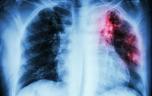

Tuberculose : une des maladies contagieuses les plus meurtrières

La tuberculose est une infection liée au bacille de Koch qui touche en priorité les poumons, ce qui la rend contagieuse quand les malades toussent. L’émergence du SIDA et des résistances aux antibiotiques rend cette affection menaçante, y compris dans les pays développés.

Les organes les plus souvent atteints par l’infection tuberculeuse sont les poumons (plus de deux tiers des cas) : c’est la « tuberculose pulmonaire », qui est également la forme contagieuse de la maladie. La tuberculose peut également infecter les ganglions (« adénopathies »), la peau, les reins, le cerveau (« méningite »), les os, les intestins : c’est la « tuberculose extra-pulmonaire », qui est la forme non contagieuse.